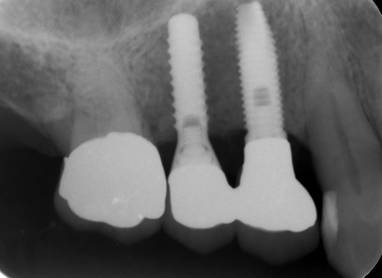

治療後。歯周病で失われた骨が回復しています。使用インプラントはスプラインツイストです。

術後。上部構造はハイブリッドレジンです。しっかり嚙めるようになり喜んでいただきました。

上部構造装着後6年。ハイブリッドレジンを使用したため、少し艶がなくなってきました。上部構造の材料には金属、ハイブリッドレジン、セラミックなどがあります。セラミックはきれいですが欠けやすいため、最近はフルジルコニアを使っています。

インプラント装着後6年。順調に経過しています。12か月毎のメインテナンスをしています。